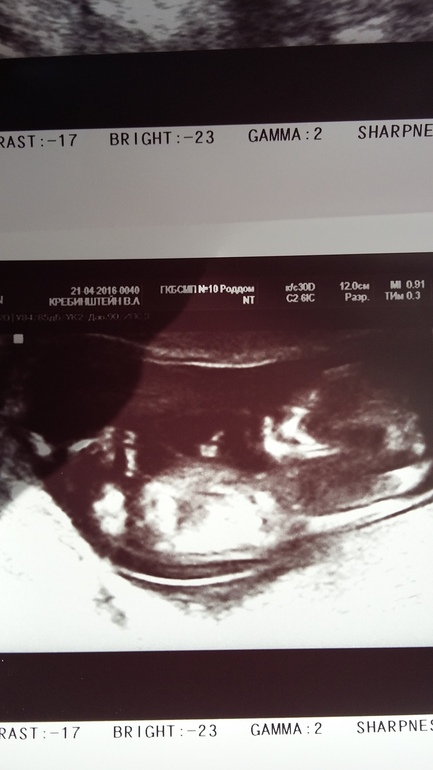

УЗИ 12 недель

Вот и наступила 38 неделя, мне как и многим тут не верится, что это случилось, но время бежит быстро и вот уже совсем скоро появится на свет наша малютка.... Вчера сходила на плановый прием в ж\к измерили ОТ 100, ВДМ 41 это +2 см с прошлой недели, хотя прибавка в весе всего 200 гр. Общая прибавка около 10 кг. Если честно я очень надеялась родить на этой неделе, я одна из тех кто хотел ребенка знака Весы. Но сегодня все мои надежды на скорые роды были развеяны..... Съездила я в роддом на осмотр и УЗИ. УЗИ показало, что головка еще очень высоко, девочка наша чувствует себя прекрасно, так как с плацентой у меня тоже все хорошо (за это переживала, была плацентарная недостаточность). Вес малышки приблизительно 3300-3400. Еще сказали длинноногая, не в маму)))) (у меня рост 156). Вот думаю зря я столько вещей 56 размера купила......Еще сказали, что есть обвитие и вод многовато, хотя многоводье не ставят. После был осмотр на кресле, который только подтвердил, что в ближайшие 2 недели я не рожу, шейка длинная твердая и закрытая.... Так что ходить нам до ПДР 2 ноября...Значит быть мне мамой маленького Скорпиончика.....Не смотря на то что набрала я не много эти две недели придется себя ограничивать в еде, так как дочка очень хорошо набирает, а родить мне нужно самой и без разрезов и разрывов......Так что остаюсь в сообществе минимум на две недели и продолжаю наслаждаться своим положением.....